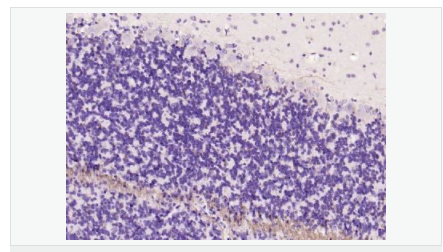

| 產品應用 | WB=1:500-2000 ELISA=1:5000-10000 IHC-P=1:100-500 IHC-F=1:100-500 Flow-Cyt=1ug/test IF=1:100-500 (石蠟切片需做抗原修復) not yet tested in other applications. optimal dilutions/concentrations should be determined by the end user. |

| 產品介紹 | The classic group of Myelin basic protein (MBP) isoforms (isoforms 4 to 14) are with PLP the most abundant protein components of the myelin membrane in the CNS. They have a role in both its formation and stabilization. The smaller isoforms might have an important role in remyelination of denuded axons in multiple sclerosis. The non classic group of MBP isoforms (isoforms 1 to 3/Golli MBPs) may preferentially have a role in the early developing brain long before myelination, maybe as components of transcriptional complexes, and may also be involved in signaling pathways in T cells and neural cells. Differential splicing events combined to optional posttranslational modifications give a wide spectrum of isomers, each of them having maybe a specialized function. Function: The classic group of MBP isoforms (isoform 4-isoform 14) are with PLP the most abundant protein components of the myelin membrane in the CNS. They have a role in both its formation and stabilization. The smaller isoforms might have an important role in remyelination of denuded axons in multiple sclerosis. The non-classic group of MBP isoforms (isoform 1-isoform 3/Golli-MBPs) may preferentially have a role in the early developing brain long before myelination, maybe as components of transcriptional complexes, and may also be involved in signaling pathways in T-cells and neural cells. Differential splicing events combined with optional post-translational modifications give a wide spectrum of isomers, with each of them potentially having a specialized function. Induces T-cell proliferation. Subunit: Homodimer. Isoform 3 exists as a homodimer. Subcellular Location: Myelin membrane; Peripheral membrane protein; Cytoplasmic side. Note=Cytoplasmic side of myelin. Tissue Specificity: MBP isoforms are found in both the central and the peripheral nervous system, whereas Golli-MBP isoforms are expressed in fetal thymus, spleen and spinal cord, as well as in cell lines derived from the immune system. Post-translational modifications: Several charge isomers of MBP; C1 (the most cationic, least modified, and most abundant form), C2, C3, C4, C5, C6, C7, C8-A and C8-B (the least cationic form); are produced as a result of optional PTM, such as phosphorylation, deamidation of glutamine or asparagine, arginine citrullination and methylation. C8-A and C8-B contain each two mass isoforms termed C8-A(H), C8-A(L), C8-B(H) and C8-B(L), (H) standing for higher and (L) for lower molecular weight. C3, C4 and C5 are phosphorylated. The ratio of methylated arginine residues decreases during aging, making the protein more cationic. The N-terminal alanine is acetylated (isoform 3, isoform 4, isoform 5 and isoform 6). Arg-241 was found to be 6% monomethylated and 60% symmetrically dimethylated. Phosphorylated by TAOK2, VRK2, MAPK11, MAPK12, MAPK14 and MINK1. Similarity: Belongs to the myelin basic protein family. SWISS: N/A Gene ID: 100731253 Database links: Gene ID: 100731253 Guinea pig Entrez Gene: 4155 Human Entrez Gene: 17196 Mouse Omim: 159430 Human SwissProt: P02686 Human SwissProt: P04370 Mouse SwissProt: P25274 Rabbit Unigene: 551713 Human Unigene: 63285 Rat Important Note: This product as supplied is intended for research use only, not for use in human, therapeutic or diagnostic applications. 神經生物學相關蛋白(Neurobiology) 少突膠質細胞標志物 主要用于脊髓脫髓鞘病-脊髓多發(fā)硬化癥的研究。 MBP髓鞘堿性蛋白和髓鞘相伴糖蛋白是多發(fā)性硬化的自身免疫攻擊的靶。 Myelin basic protein (MPB) :Oligodendrocyte Protein produced by mature oligodendrocytes; located in the myelin sheath surrounding neuronal structures 髓磷脂Myelin/oligodendrocyte specific protein (MOSP)是由中樞神經系統(tǒng)中少突膠質細胞和外周神經系統(tǒng)中雪旺氏細胞產生特殊蛋白質。是形成髓鞘的主要成分,對于引導神經沖動的傳遞起著致關重要的作用。 多年來,關于髓鞘的形成機理和與其相關的一些先天性疾病的發(fā)病機制一直是眾多科學家關注的重點。如:多重硬化癥和腦白質營養(yǎng)不良等,都與神經系統(tǒng)的去髓鞘化相關。 |